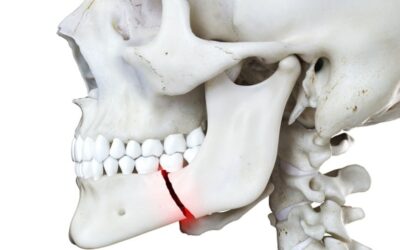

Κατάγματα οστών προσώπου

Στη χώρα μας, ως πρώτη αιτία των καταγμάτων στην περιοχή του προσώπου και ειδικότερα στην κάτω γνάθο είναι τα τροχαία ατυχήματα. Ακολουθούν: η άσκηση βίας, οι πτώσεις, τα εργατικά-βιομηχανικά ατυχήματα, τα αθλητικά ατυχήματα (παρουσιάζουν τάση αύξησης), οι...